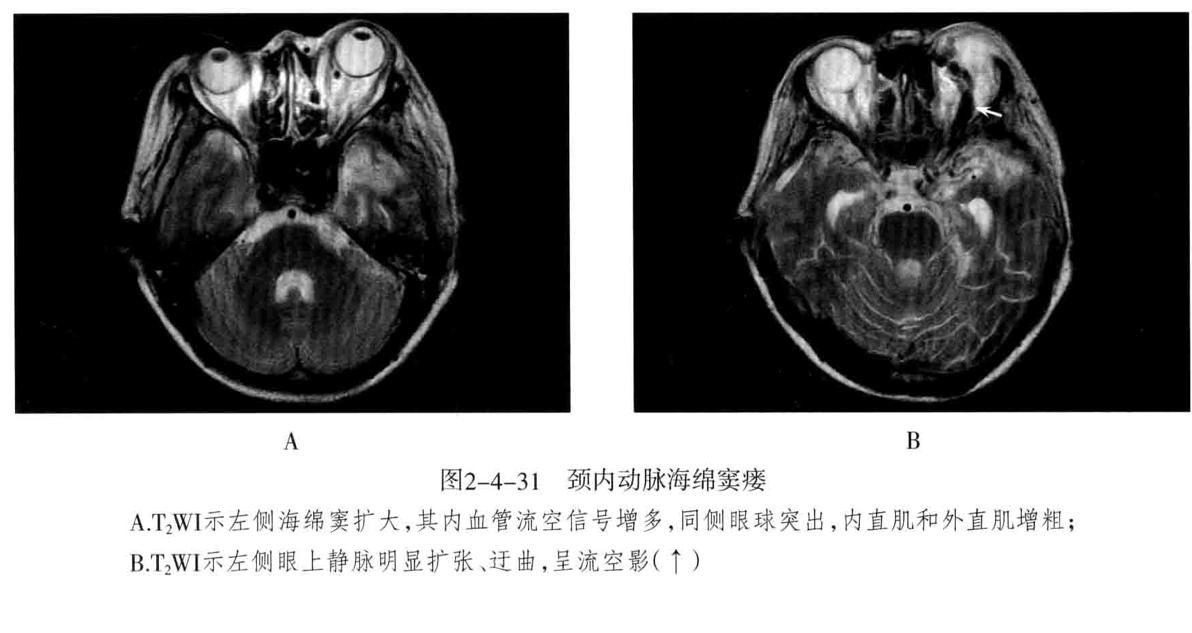

颈内动脉海绵窦瘘: 定义:指海绵窦段的颈内动脉及其分支破裂,与海绵窦之间形成动静脉的异常沟通所引起的一组神经眼科综合征。75%以上由外伤性引起,多为单侧发病,眼部征像多出现在患侧。

2. MRI:海绵窦扩大,海绵窦内血管影增多,且迂曲、粗大、不规则。同侧眼上静脉明显扩张,呈迂曲的流空信号。眼外肌增粗充血和眼球突出。需与海绵窦肿瘤性病变鉴别。